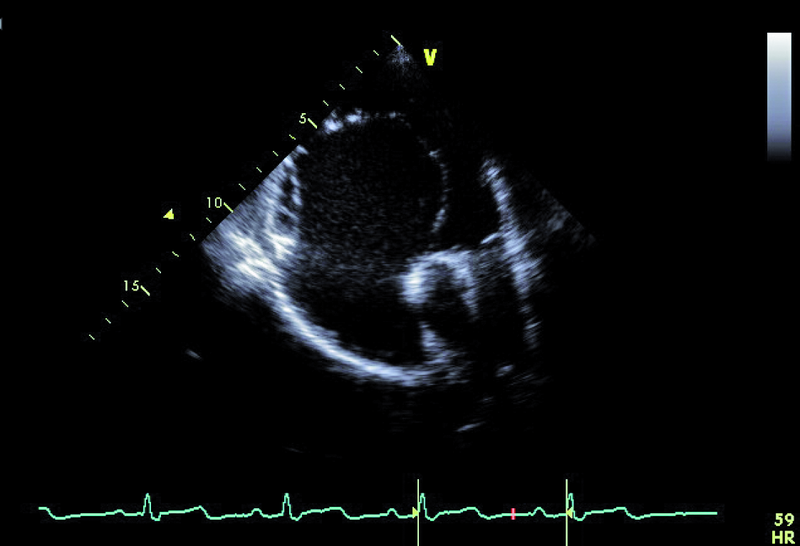

Cechy anomalii Ebsteina łatwo zidentyfikować. Należy zwrócić uwagę na odległość między przyczepem płatka przegrodowego zastawki trójdzielnej a przyczepem przedniego płatka zastawki mitralnej (ryc. 1). Fizjologiczne przesunięcie płatków jest niewielkie i zwykle nie przekracza 5-10 mm. Za kryterium rozpoznania anomalii uważa się wartość 20 mm (w przedstawionym przypadku 50 mm). Przemieszczone płatki są zwykle zmienione organicznie, pogrubiałe, często pociągane przez struny ścięgniste. Płatek przedni jest prawidłowo przyczepiony do pierścienia zastawki trójdzielnej, natomiast jest zwykle powiększony i kształtem może przypominać żagiel (ryc. 1-3). Cechą płatka przedniego w anomalii Ebsteina jest także jego nadmierna ruchomość i liczne perforacje powodujące zwykle więcej niż jedną falę zwrotną (ryc. 4). Zatrializowana część prawej komory znajduje się między przemieszczonymi przyczepami płatków przegrodowego i tylnego, a właściwa jama ma zmniejszoną pojemność. To, czy wada daje objawy, zależy od nasilenia niedomykalności trójdzielnej i od współistniejących anomalii. Niedomykalność trójdzielna u tego pacjenta, mimo dużego przemieszczenia płatka przegrodowego, była mała (ryc. 4). Zarejestrowany metodą doplerowską profil prędkości z jednego ze strumieni niedomykalności wskazywał na niepodwyższone ciśnienie w jamie prawej komory (ryc. 5). Funkcja mięśnia prawej komory określona za pomocą pomiaru przemieszczenia bocznej części pierścienia zastawki trójdzielnej była prawidłowa (ryc. 6). Diagnostykę można na tym etapie zakończyć i uznać, że chory kwalifikuje się do dalszej obserwacji. Badanie przezprzełykowe jest potrzebne u pacjentów, u których nie można ocenić dokładnie morfologii zastawki trójdzielnej. Może też być konieczne w przypadku desaturacji krwi tętniczej i podejrzenia często towarzyszącego anomalii ubytku przegrody międzyprzedsionkowej. Warto zaznaczyć, że ubytek zwykle charakteryzuje się przeciekiem prawo-lewym, na skutek dysfunkcji jam prawego serca i wzrostu ciśnienia w jamie prawego przedsionka. W tym przypadku, wobec braku sinicy, badania przezprzełykowego nie wykonano. Cewnikowanie serca także nie jest konieczne, ponieważ chory ma małą niedomykalność trójdzielną i dobrą wydolność fizyczną, a więc nie kwalifikuje się do leczenia operacyjnego.